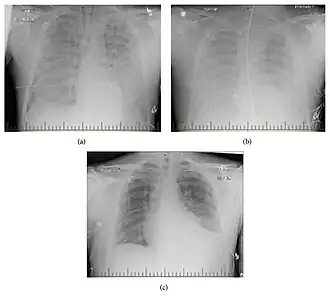

| Progression of hantavirus pulmonary syndrome | |

Hantavirus pulmonary syndrome (HPS), also called hantavirus cardiopulmonary syndrome (HCPS), is a severe respiratory disease caused by hantaviruses. The main features of illness are microvascular leakage and acute respiratory distress syndrome. Symptoms occur anywhere from one to eight weeks after exposure to the virus and come in three distinct phases. First, there is an early phase with flu-like symptoms such as fever, muscle aches, headache, and shortness of breath, as well as low platelet count. Second, there is cardiopulmonary phase during which people experience elevated or irregular heart rate, cardiogenic shock, and pulmonary capillary leakage, which can lead to respiratory failure, low blood pressure, and buildup of fluid in the lungs and chest cavity. The final phase is recovery, which typically takes months, but difficulties with breathing can persist for up to two years. The disease has a case fatality rate of 30 to 60 percent. Death usually occurs suddenly during the cardiopulmonary phase.

HPS symptoms occur about 1–8 weeks after exposure to the virus. The main features of the illness are microvascular leakage and acute respiratory distress syndrome (ARDS). The disease has three phases: early (prodromal), cardiopulmonary, and recovery. Prodromal symptoms last for 1–5 days[1] and include flu-like symptoms such as fever, headache, muscle pain (myalgia), nausea, vomiting, dizziness, chills, coughing, and shortness of breath (dyspnea), as well as low platelet count in the blood (thrombocytopenia).[2][3][4] Within 10 days, the cardiopulmonary phase begins[5] and lasts for several days. It is marked by elevated heart rate (tachycardia), irregular heartbeats (arrhythmias), and cardiogenic shock, a condition in which the heart is unable to pump enough blood for the body. Pulmonary capillary leakage can lead to respiratory failure, buildup of fluids in the lungs (pulmonary edema), low blood pressure (hypotension), and buildup of fluid in the chest cavity between the lungs and chest wall (pleural effusion).[2][3][4]